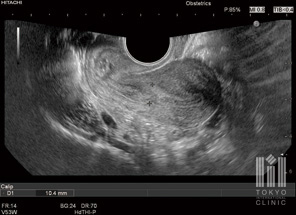

経膣超音波検査

指の太さほどの器具を膣内に入れて子宮や卵巣を観察します

- 経腟超音波